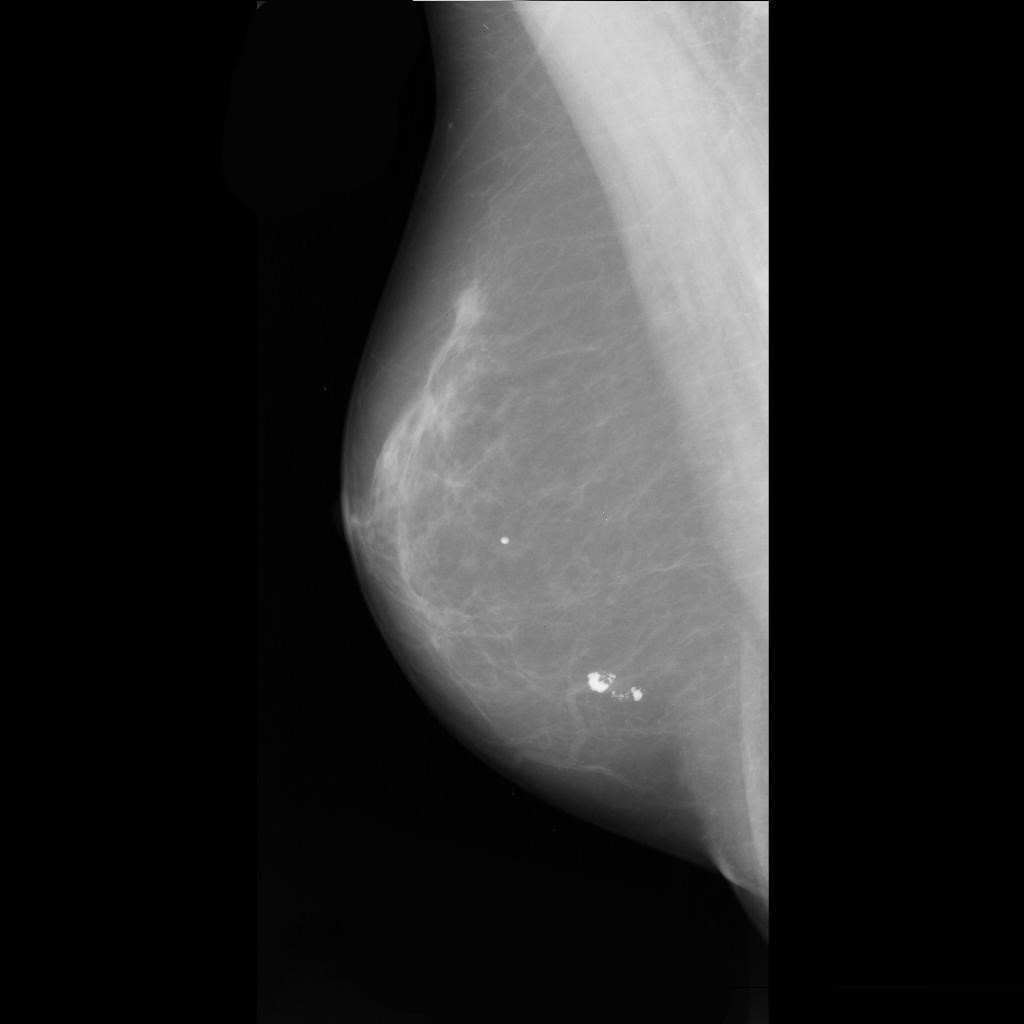

benign

malignant